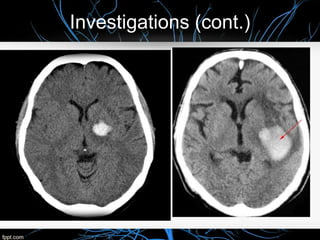

Infarction appears as hypodense (more dark) area on CT

Hemorrhage appeare as hyperdesne (bright) area on CT